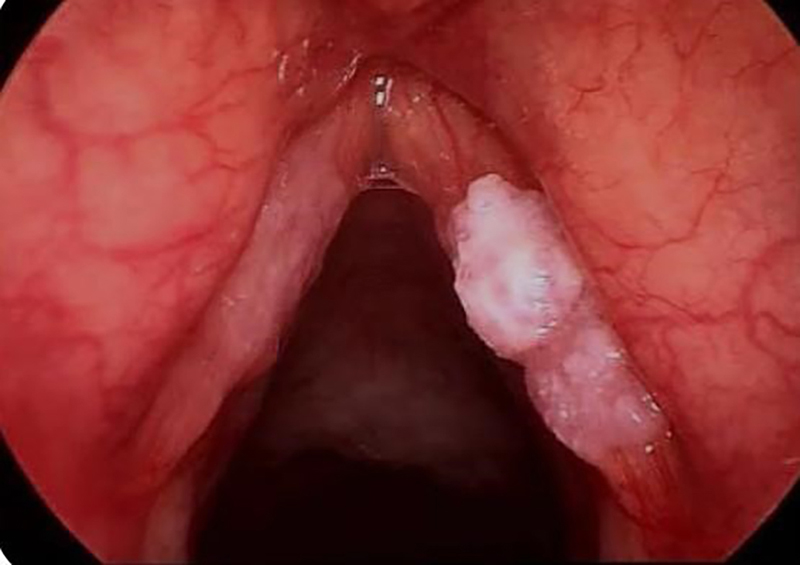

This patient came to the Respiratory Medicine outpatient department with complaints of cough with expectoration and throat pain over 15 days, a change in voice (hoarseness) with difficulty in swallowing (solids > liquids) for 1 month, weight loss of 9 kgs in 2 months, regurgitation (liquids > solids) for 15 days. A chest X-ray revealed bilateral heterogenous opacities (Figure 1) and sputum was sent for routine investigations. Sputum CBNAAT report detected M. tuberculosis without RiF resistance. Computed tomography of the neck revealed asymmetric heterogeneously thickening, involving both lateral glosso-epiglottic folds, the epiglottis, aryeepiglottic folds (R > L) with obliteration of pyriform fossa. Cervical nodes were mildly enlarged, which suggested a possible neoplasm. The patient underwent endoscopy that revealed ulceroproliferative growth on bilateral aryepiglottic folds, arytenoids, pyriform fossa, and vocal cords (Figure 2).

Figure 1

Figure 1. Chest x-ray reveals bilateral upper lobe infiltrates with cavities, especially in the left upper lobe.